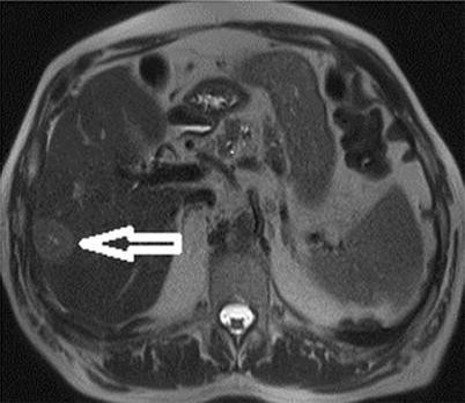

–MRI: markedly T2 hyperintense (light-bulb bright)

T2: Two rounded lesions following fluid signal seen at segment 2 and 6 of the liver.